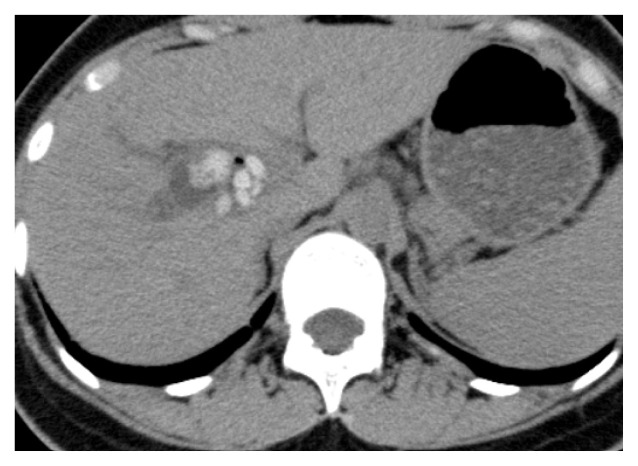

Long-term complications were identified in two patients. One patient with Todani IV-A disease underwent radical surgery at 1 year of age. Multiple intrahepatic stones were detected in the right hepatic duct during postoperative follow-up examinations (Figure 2). However, the patient did not have any symptoms and had normal blood test results for 25 years. The patient deferred treatment as she was asymptomatic. Therefore, only observation has been continued until now.